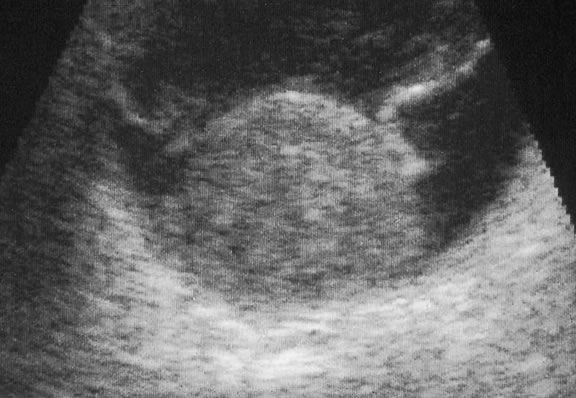

Ultrasonography can support the diagnosis of ciliary body or choroidal melanoma and is a particularly helpful way of disclosing tumors in eyes with opaque media.54 Ultrasonographic studies can alsodemonstrate areas of extrascleral extension. A scan ultrasonography shows a high internal spike and low internal reflectivity. B scan ultrasonography shows characteristic acoustic hollowness and choroidal excavation (Fig. 23). Hemangiomas and metastases usually appear acoustically solid because they contain multiple acoustic interfaces.

Fig. 23. B-scan ultrasound, choroidal melanoma.